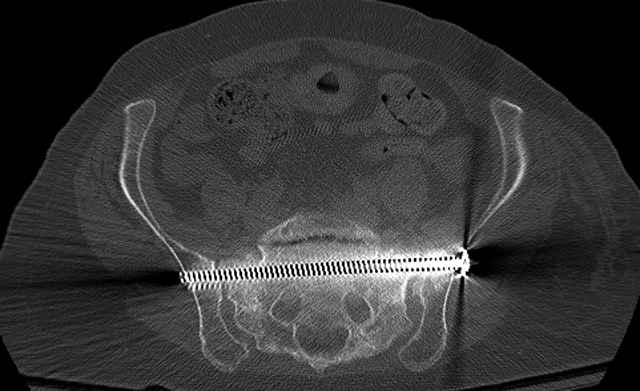

Here are a recent patient’s example slides...

54 yo Female Fell c/o Pain

Percutaneous Fixation

(B) Ramus-Retrograde

2 TransIliac-TransSacral

Upper Segment